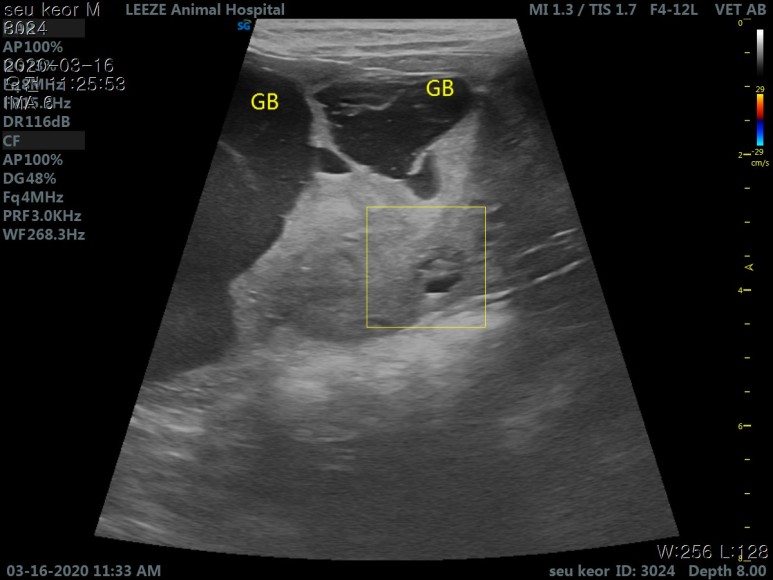

초음파를 보니..

담낭이 확장 된것 외에도 비정상적으로 커보이는 물주머니 형상의 것이 관찰 됩니다

그리고 병원에서는 이것이 담낭의 확장인지 혹은 간인지? 혹은 간외에 따로 생긴 세포덩어리 (종양)인지

간 이라면. 갈비뼈 아래까지 너무나 비대해진 이런 현상을 본적이 없다

결과적으로 의심되는것은 '간종양' 하지만, 사진상 슬러지가 심해 우선은 급한 황달수치를 수액으로 잡아보고

좀더 추이를 지켜보자

하지만, 다음날, 황달 수치는 치솟았고, 시간을 벌기 위해 더 정밀장비가 있는 2차병원에서 더 고급 장비로

초음파 진단후 '간종양 을 확진' 받음.